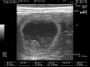

היום נעשתה בנוסף גם סריקה של האשכים ובלוטת הפרוסטטה של סילבר שלוקח גם הוא כמו מארם חלק במחקר הקשור ללימודי (רפואה וטרינרית) בנושא הריון והמלטה בכלבות. שני האשכים של סילבר הראו גדלים תואמים ואחידות בריקמה – דבר שנצביע על בריאות מושלמת מבחינה מינית. לרוב בכלבים בגיל הזה (5 שנים) כבר מתחילות ציסטות קטנות שאומנם אינן מסוכנות בשלב הזה אך מחייבות מעקב צמוד. בפרוסטטה של סילבר היתה מעט גדולה מה"נורמה" אך הדבר סביר בהחלט בהתחשב בפעילות המוגברת שהיתה לו לפני כחודש (בהרבעה הרצופה 5 ימים) ובעוד כחצי שנה יעבור סריקה נוספת כדי לעקוב אחרי המצב ולוודא שהבלוטה פועלת כראוי. בעיות פרוסטטה קיימות בכל הכלבים שאינם מסורסים (ללא יוצאים מן הכלל) ותלוייה בעיקר בגיל וברמת הפעילות המינית שהכלב מבצע – גיל מבוגר ופעילות מוגברת מעלים את הסיכון.